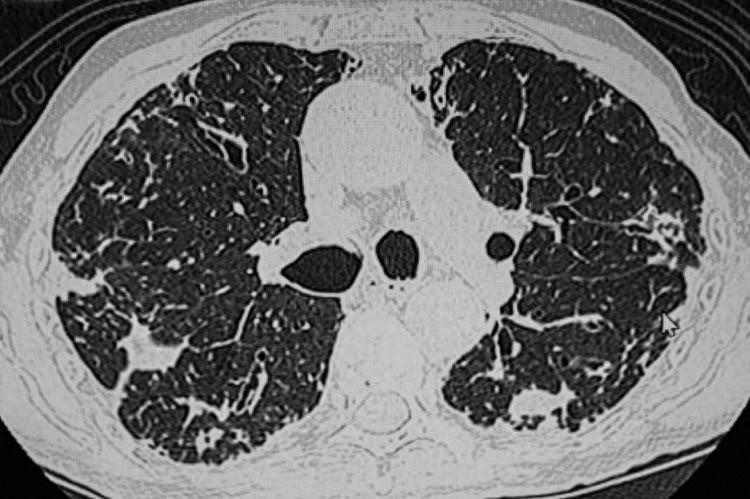

肺結節是指肺部出現的直徑≤3cm的不規則型病竈,影像學檢查中爲密度增高的陰影,直徑在2cm以下的一般爲良性結節。肺部結節是否爲惡性,需要動態觀察,如果在短期內體積增大、密度增高以及發生了形態變化,則要高度警惕可能是惡變了